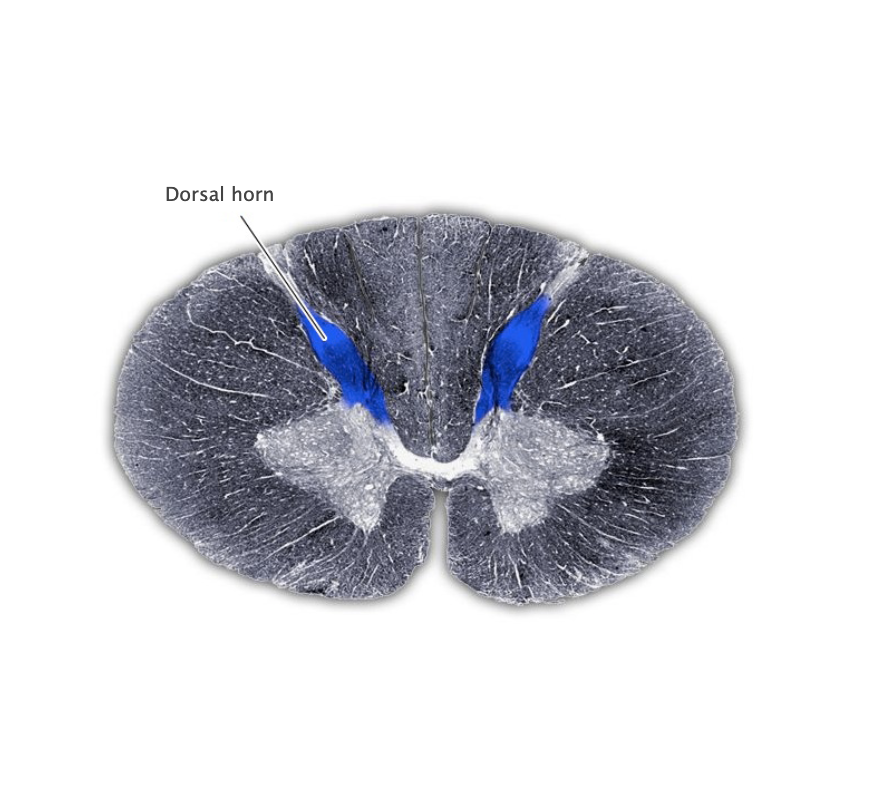

Dorsal horn

The dorsal (sensory) portion of the spinal cord gray matter.